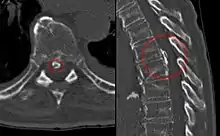

Imaging

Magnetic resonance imaging (MRI) is the preferred modality for the evaluation of back pain and visualization of bone, soft tissue, nerves and ligaments. X-rays are a less costly initial option offered to patients with a low clinical suspicion of infection or malignancy, and they are combined with laboratory studies for interpretation.

Imaging is not warranted for most patients with acute back pain. Without signs and symptoms indicating a serious underlying condition, imaging does not improve clinical outcomes in these patients. Four to six weeks of treatment is appropriate before consideration of imaging studies. If a serious condition is suspected, MRI is usually most appropriate. Computed tomography is an alternative if MRI is contraindicated or unavailable.[37] In cases of acute back pain, MRI is recommended for those with major risk factors or clinical suspicion of cancer, spinal infection or severe progressive neurological deficits.[38] For patients with subacute to chronic back pain, MRI is recommended if minor risk factors exist for cancer, ankylosing spondylitis or vertebral compression fracture, or if significant trauma or symptomatic spinal stenosis is present.[38]

Early imaging studies during the acute phase do not improve care or prognosis.[39] Imaging findings are not correlated with severity or outcome.[40]

Infection

Common infectious causes of back pain include osteomyelitis, septic discitis, paraspinal abscess and epidural abscess.[19] Infectious causes that lead to back pain involve various structures surrounding the spine.[27]

Osteomyelitis is the bacterial infection of the bone. Vertebral osteomyelitis is most commonly caused by staphylococci.[19] Risk factors include skin infection, urinary tract infection, IV catheter use, IV drug use, previous endocarditis and lung disease.

Spinal epidural abscess is commonly caused by severe infection with bacteremia. Risk factors include recent administration of epidurals, IV drug use or recent infection.